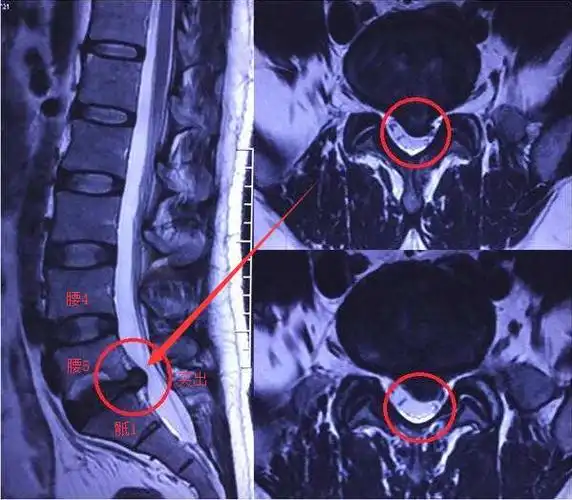

病例:椎间孔镜技术治愈腰4/5,腰5/骶1椎间盘突出症

行ct检查示:腰4/腰5,腰5/骶1椎间盘突出,需住院进一步治疗.

看下图,腰4,腰5,骶1的位置,以及红色箭头所指的腰5骶1突出的位置.